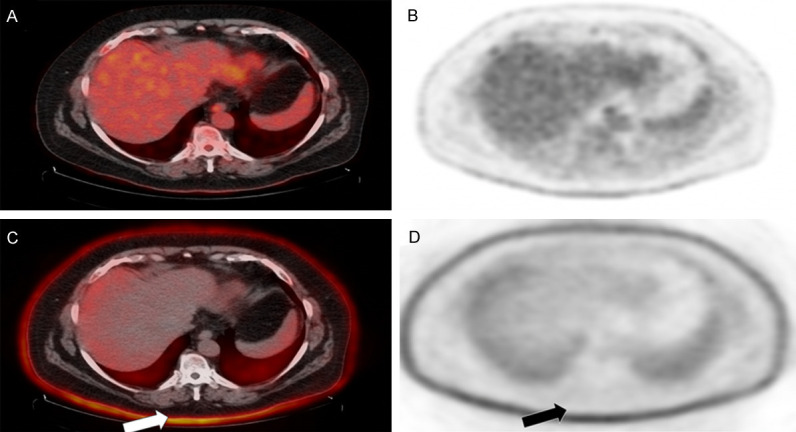

Figure 1.

Focal areas of cutaneous radiotracer uptake on FDG-PET/CT. Non-attenuation-corrected images (A, B) demonstrate higher uptake than the attenuation-corrected images (C, D) in the corresponding areas of psoriatic skin lesions.